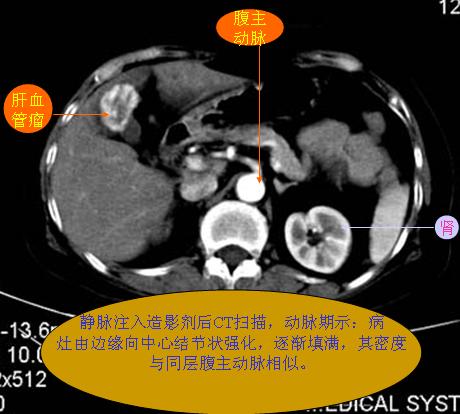

腹部ct解剖与基本病变